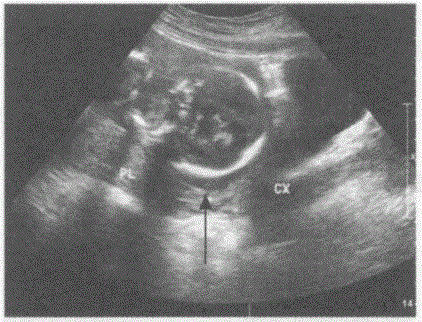

问题 临床资料:女,24岁,孕19周。 超声综合描述:胎盘位于后壁,厚度2.7cm,胎盘下缘抵宫颈内口边缘(箭头所示)。 超声提示:

选项 A.宫内中孕边缘性前置胎盘 B.宫内中孕低置胎盘 C.宫内中孕部分性前置胎盘 D.宫内中孕中央性前置胎盘

答案 A